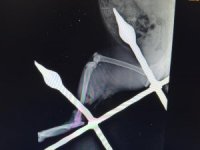

Mersin’de saplandığı demirden kurtarılan kedi sağlığına kavuştuMersin'de bir apartmanın demir korkuluklarına bacağı saplanan ve itfaiye ekipleri tarafından kurtarılan kendi, tedavisinin ardından sağlığına kavuştu.15 Şubat 2024 Perşembe 11:28